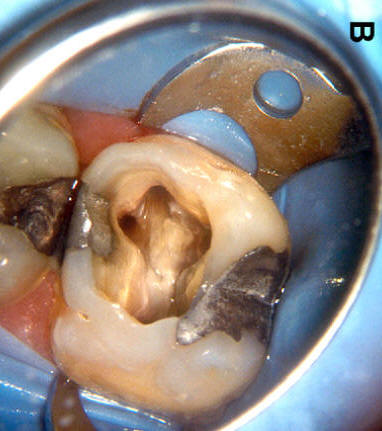

Primer molar superior Presenta tres raíces, las cuales se distribuyen dos vestibulares y una palatina. La raíz mesiovestibular es achatada en sentido mesiodistal y amplia en sentido vestibulopalatino.El conducto mesiovestibular con frecuencia es curvo y de sección en forma de hendidura. La existencia de dos conductos en esta raíz, puede presentar la siguiente configuración:

Estos conductos pueden unirse a distintos niveles, terminando en un foramen único o ser de trayectoria independiente hasta el ápice y terminar en forámenes separados. Son atrésicos y de difícil tratamiento en especial el palatino. La raíz distovestibular tiene dimensiones menores que la mesiovestibular y no presenta curvaturas acentuadas. El conducto distovestibular (Color verde) por lo general es atrésico y puede presentar curvaturas. La raíz palatina es la más voluminosa de forma cónica y sección circular. Puede ser recta o curva. Cuando es curva, el sentido e la curva es hacia vestibular. El conducto palatino (Color rojo) es amplio y de fácil acceso, rectilíneo o con una curva leve hacia vestibular. |